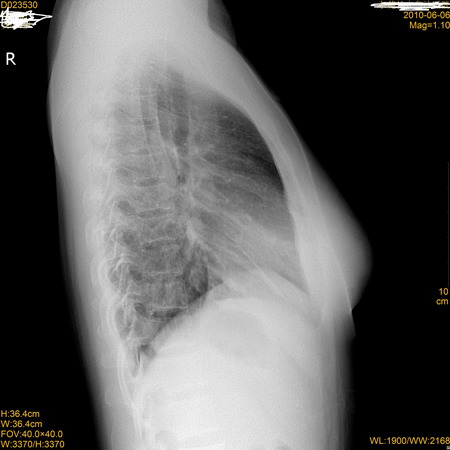

标题: X7496:看看这张胸片!然后再看其CT片!

同行们再看看做的ct片,真的能看到很多,平片也能看到点,你说呢?

右下肺近心缘旁可见-类圆形高密度影,但侧位片上没有看见,建议ct

左下肺炎性改变;没有必要做ct了。右肺无异常。

左下肺炎性改变,请复查。

右侧心缘欠清晰,右下肺炎症?